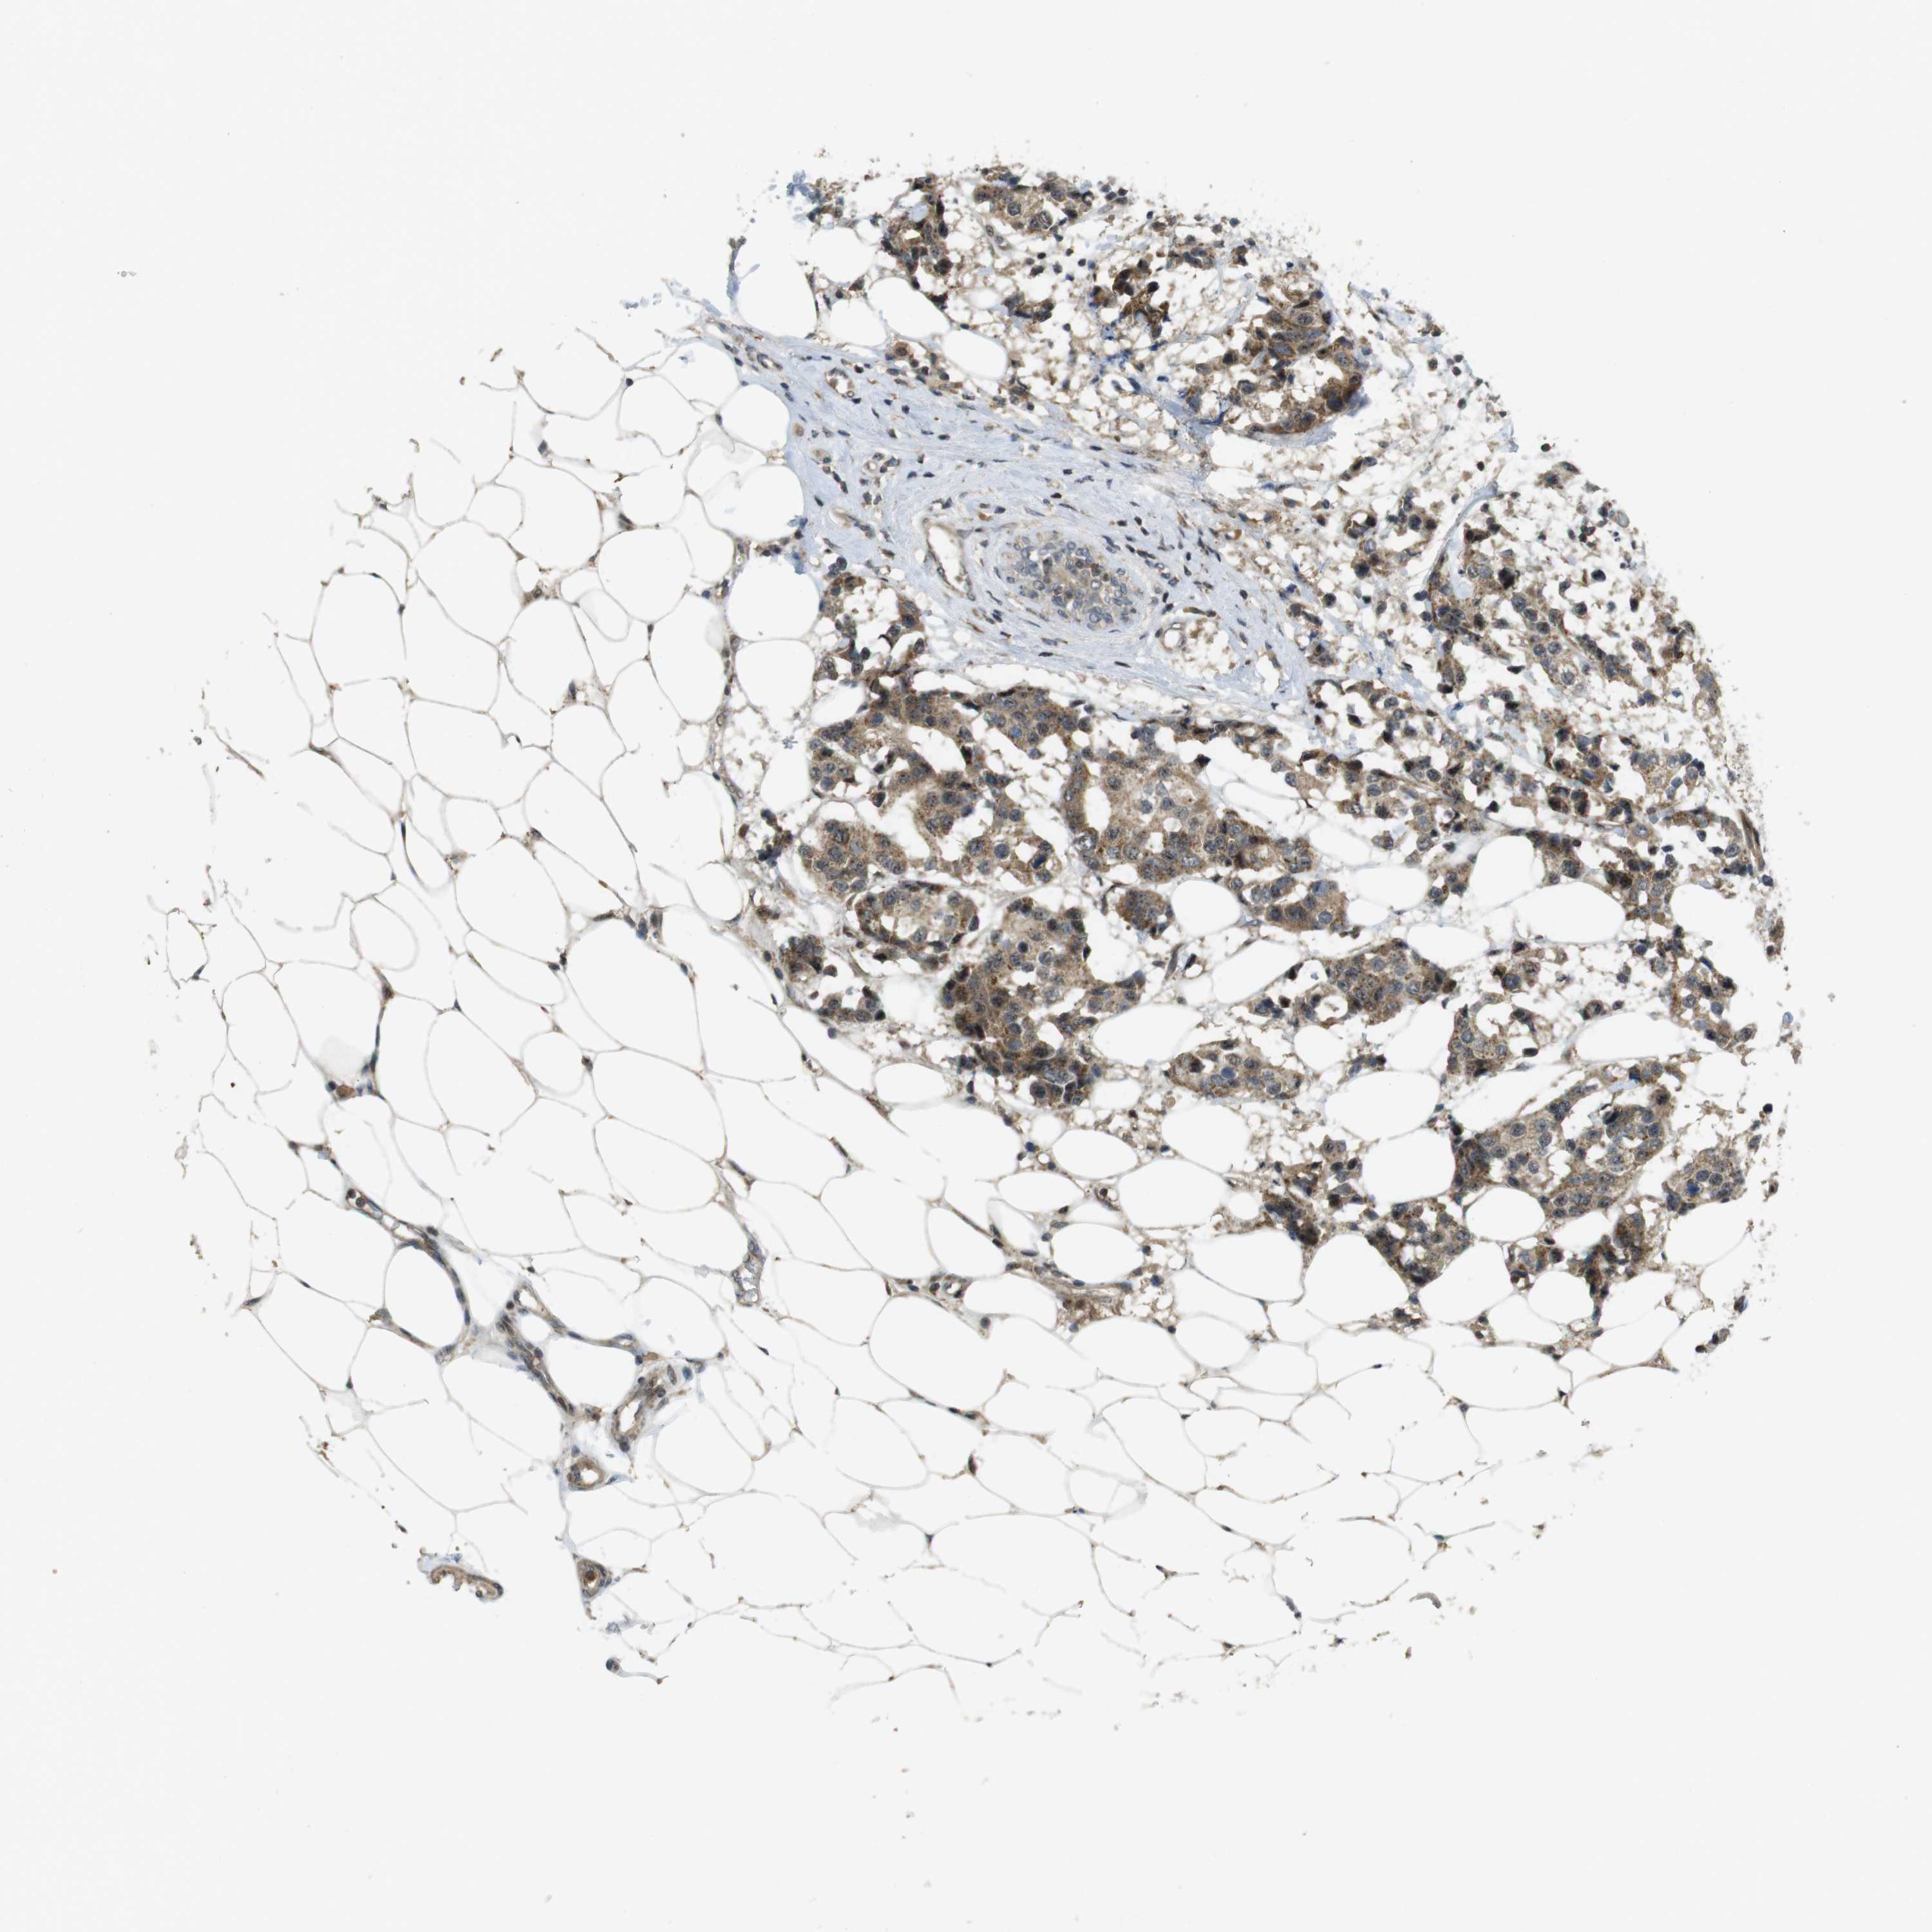

BRCA TCGA BRCA VALIDATION PROTEIN EXPRESSION

Breast cancer

Human cancer